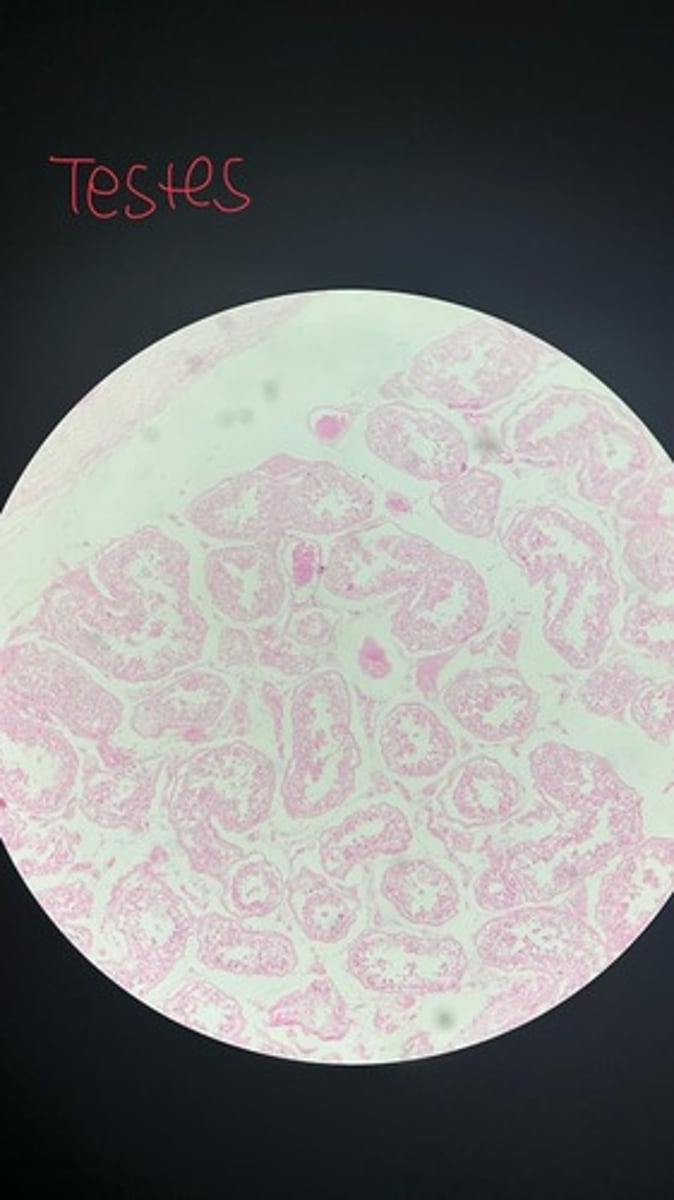

Testes HE

Testes HE

Testes HE

Testes HE

Testes HE